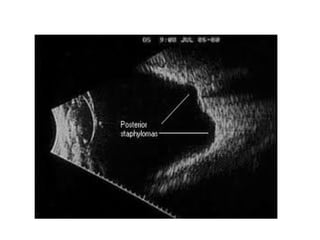

• Posterior Staphyloma

• The posterior staphyloma is a pathognomonic feature of eyes with pathologic myopia. It is a

localized

• ectasia of the sclera, choroids, and retinal pigment epithelium that can be of variable size and

involve different aspects of the posterior fundus.

• These staphylomas are best observed with indirect binocular ophthalmoscopy and B-scan

ultrasonography.

• The posterior staphylomas are usually present from a young age and

• may progress with age, particularly with high myopias and long axial

• lengths.

• Vision progressively deteriorates in eyes with staphylomas that amacula-centered because of

the progressive thinning of the choroids and

• retinal pigment epithelium in the macula.

POSTERIOR STAPHYLOMA: Staphylomas are localized ectasia (“enlargement”) of the

sclera, choroid, and RPE. It can be easily seen on B-scan or a CT Scan. Staphylomas can

• Posterior Staphyloma •The posterior staphyloma is a pathognomonic feature of eyes with pathologic myopia. It is a localized • ectasia of the sclera, choroids, and retinal pigment epithelium that can be of variable size and involve different aspects of the posterior fundus. • These staphylomas are best observed with indirect binocular ophthalmoscopy and B-scan ultrasonography. • The posterior staphylomas are usually present from a young age and • may progress with age, particularly with high myopias and long axial • lengths. • Vision progressively deteriorates in eyes with staphylomas that amacula-centered because of the progressive thinning of the choroids and • retinal pigment epithelium in the macula.

POSTERIOR STAPHYLOMA: Staphylomasare localized ectasia (“enlargement”) of the sclera, choroid, and RPE. It can be easily seen on B-scan or a CT Scan. Staphylomas can eventually lead to atrophy and loss of vision.